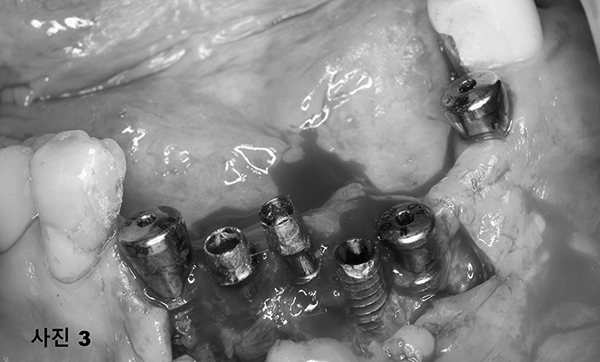

(사진3) 그 부위를 열어보니 너무 촘촘히 박히고 임플란트를 제대로 식립 못하여 임플란트의 나사선들이 잇몸뼈에 제대로 들어가 있지 못하고 밖으로 노출되어 있었다.

저렴한 임플란트를 선전하는 병원들에서 임플란트를 필요이상의 박리다매의 현상을 보여주고 있다.

환자의 아래턱 뼈의 상태가 심한감염에 의하여 임플란트를 더 이상 심지 못하기에 양쪽 구치부위에 5개를 식립하고,

풀아치 고정성 보철물을 하여주기로 하였다. 국소마취후, (사진4)와 같이 감염된 모든 임플란트를 제거 후,